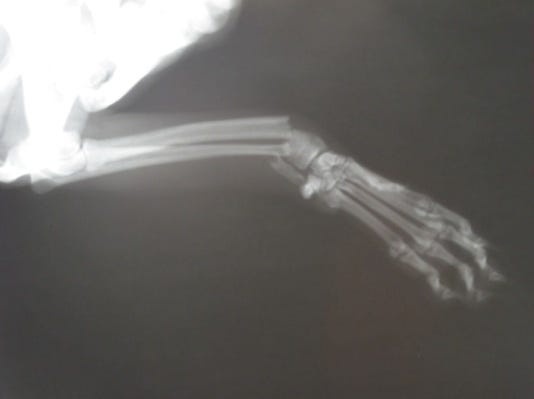

Диагностика

Мы используем клинико-ортопедическое обследование и рентгенографию конечности в двух взаимоперпендикулярных проекциях для выявления сложности перелома и степени смещения костных отломков, что и определит дальнейший метод лечения перелома.

Наиболее типичным переломом у карликовых пород собак является поперечный простой перелом костей предплечья в нижней трети (на фото).